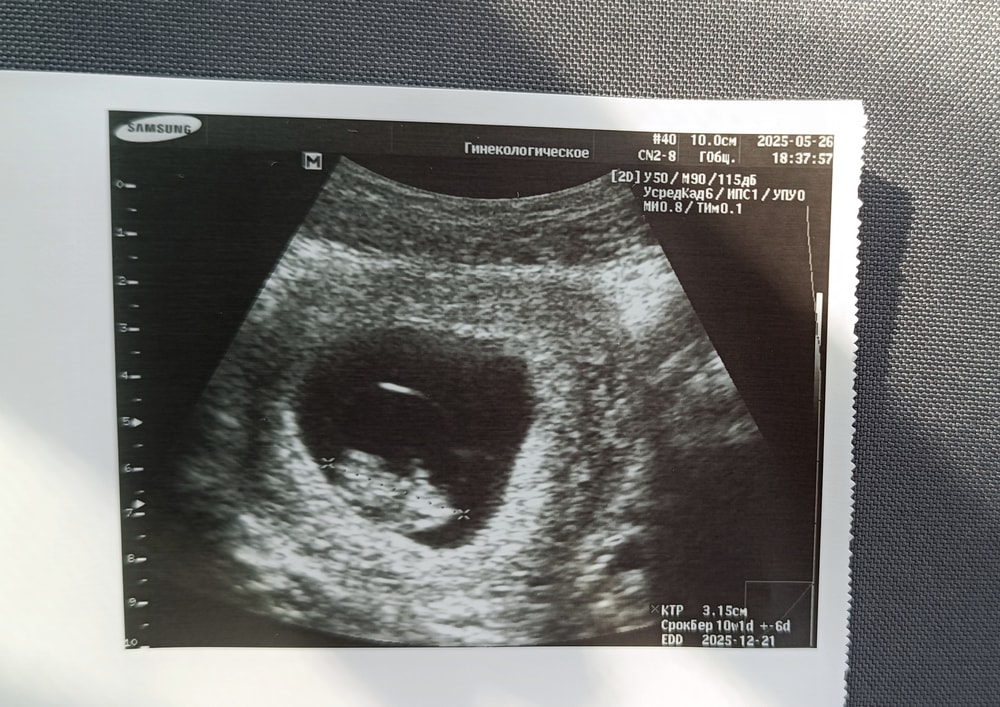

Контрольное УЗИ перед НИПТ 9.3 недели

Наши будни, наши неделькиВчера ходила на УЗИ, по ктр детка-конфетка опережает развитие на 4 дня. Посмотрели, насколько это возможно твп - не увеличено. Но как я понимаю, твп до 11 недели не информативно. Потащила на УЗИ мужа, а по итогу в клинике дали другого врача, кабинет и аппарат (дали похуже), поэтому все посмотрели за 1.5 минуты, большого экрана не было, движений конфетки не показали, в общем, муж ничего не увидел. Жаль потраченных денег на УЗИ. Но сердечко бьётся и отлично! 31 поедем сдавать кровь на Нипт в геномед. А 16 июня уже на первый скрининг.

Выделения после лютеоплацентарного сдвига так и продолжаются. Я уже больше склоняюсь, что это просто прогестероновые выделения. На УЗИ опять-таки все хорошо, тонуса нет, так что я не переживаю. В эту беременность прикрепление по передней стенке. Нужно будет следить за хорионом.